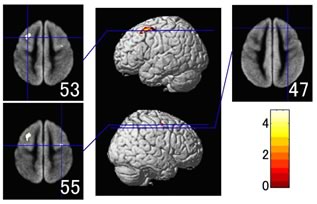

加齢による脳の萎縮の場所による違いが分かるように色分けしてみると、前頭葉やシルビウス裂付近の側頭葉で強い萎縮が起きていることが分かります。神経細胞が減ると認知など、脳が情報を処理する能力が衰えます。年をとると物覚えが悪くなることは、残念ながら、健康であっても誰にでも起こる正常な加齢変化といえます。しかし、ネットワークが減らないことは、情報の使い方は衰えないことを意味するのかも知れません。

特に前頭葉と側頭葉が加齢によって強く萎縮します。

図の上が頭、右から左へ頭頂から順に脳の水平断面を並べています。

黄色に見えるところが、より萎縮の進んでいるところ